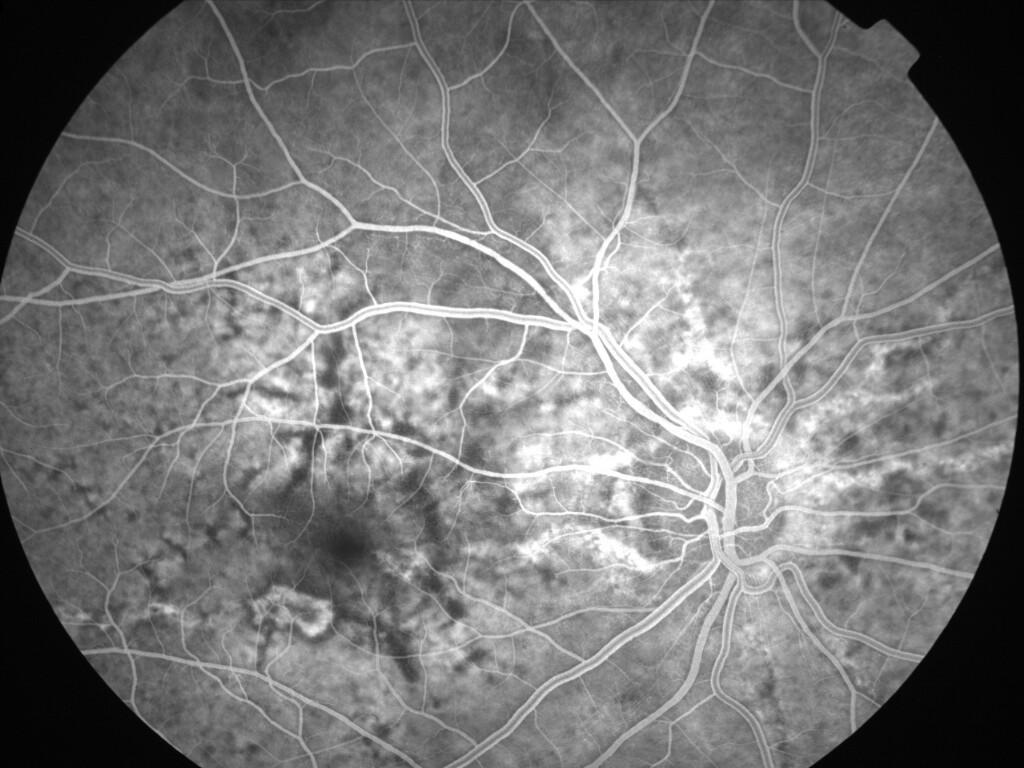

ASSOCIATION STRIES ANGIOIDES ET DYSROPHIE MACULAIRE RETICULEE

NEOVASCULARISATION